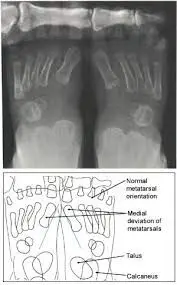

Abnormalities can been seen on x-ray even at a young age, if they are present. Abnormalities include abnormal growths, extra bones, and abnormal alignment of the the bones that are visible on x-rays films. These abnormalities can lead to symptoms such as pain, fatigue, visual deformities, and difficulty walking.

The rotation of the child's foot can also be affected by development. There are various factors determing that development from position within the uterus before birth and seating and sleeping positions after birth. If the child's feet are noticeably turning inward then an evaluation by a specialists may be necessary. If the child is excessively tripping causing other bodily injury or diffuclty with normal activity then an evaluation should be considered a necessity. There are various causes for in-toeing and should be ruled out and treated accordingly to improve activity level and prevent further injury.